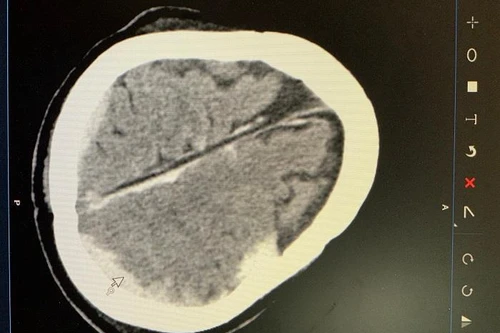

Cứu sống bệnh nhân bị tai nạn giao thông gây dập não, đa chấn thương phức tạp